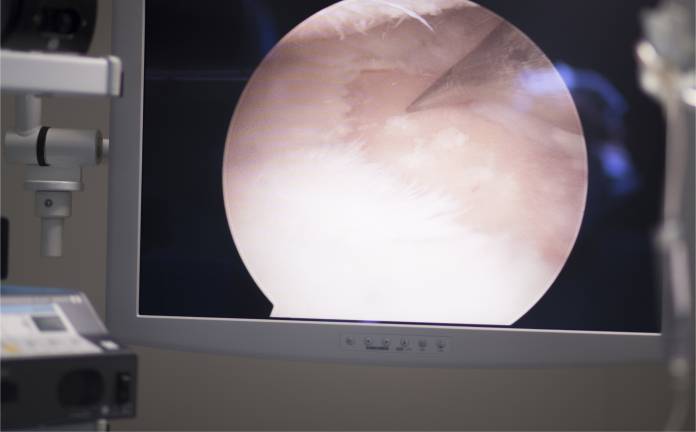

Eine Hohlnadel wird in das betroffene Gelenk gestochen, um eine Flüssigkeit (meist eine Salzwasserlösung) einzuspritzen. Daraufhin wird ein kurzer Hautschnitt angelegt, am Kniegelenk im Regelfall im vorderen äußeren Bereich, am Schultergelenk in der Regel hinten. Das Arthroskop (Spiegelungsinstrument) wird nun eingeschoben. Dies ist ein optisches Gerät (Endoskop) mit Beleuchtung, mit dem der Arzt Einblick in das Gelenk erhält und die Strukturen beurteilen kann. Flüssigkeit, bisweilen auch Gas (Kohlendioxid) wird eingeleitet, um den Einblick zu verbessern. Manchmal sind andere, nicht übliche Zugangswege nötig, um das Arthroskop einzuführen. Zusätzlich zum Arthroskop wird in den meisten Fällen ein stabartiges Instrument zum Abtasten der Gelenkinnenstrukturen eingeschoben.

Mit der Arthroskopie (Gelenkspiegelung) kann eine Untersuchung der Strukturen erfolgen, die sich im Gelenk befinden. Beurteilt werden können Gelenkinnenhaut, Gelenkknorpel, Bänder, Sehnen sowie spezielle Strukturen des jeweiligen Gelenks, z. B. die Menisken im Knie oder die Schleimbeutel-Aussackung im Schultergelenk. Im selben Eingriff können dann auch bestimmte Behandlungsmethoden zum Einsatz kommen.